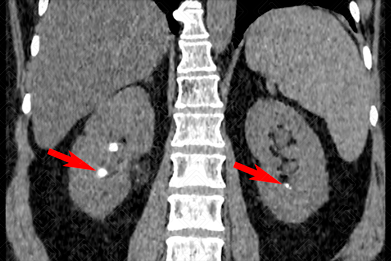

Texto alternativo para a imagem Figuras 1 e 2. Créditos: Dra. Elazir Mota - Rio de Janeiro/RJ

Descrição das figuras 1 e 2: Tomografia computadorizada de abdome, plano coronal, evidenciando cálculos renais bilaterais (setas vermelhas). Observe, ainda, a presença de cálculo coraliforme à direita, “moldando” a pelve renal (seta amarela).

• Tomografia computadorizada do abdome e pelve: E xame de escolha para avaliação de cálculos renais. Neste exame, todos os cálculos são bem visualizados já que apresentam densidade superior a 200 UH e há bom contraste com as partes moles adjacentes (a única exceção são os cálculos de Indinavir). Nestes casos, a tomografia deve ser realizada sem a administração do contraste venoso. Os cálculos apresentam-se neste exame como estruturas espontaneamente densas (f iguras acima).